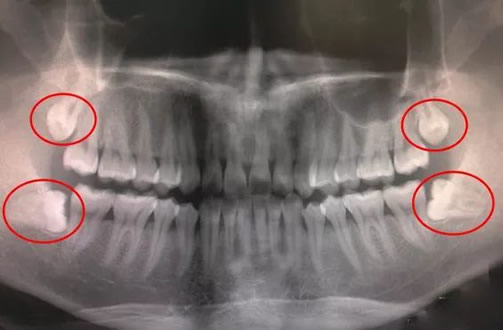

人到了一定年龄就会长出智齿,所以人们也把智齿看作是智慧和成熟的标志。但是智齿本身就没有那么友好和聪明,很多人都被智齿困扰。智齿本质上是第三磨牙。在所有牙齿中,它们是最晚萌出的,大约在20岁左右萌出,临床上这种由智齿萌出引起的冠周炎和牙龈肿痛是很常见的。当你有智齿的时候,不要以为拔和不拔是一样的,甚至不拔出来是为了省事。那那么拔智齿的危害有哪些呢?

没有正常生长的智齿,即它们没有在正确的位置生长,很容易影响相邻的牙齿。首先它会挤压附近的牙齿,使附近的牙齿松动,很容易导致牙齿在不知不觉中脱落。其次如果智齿生长的位置很不正确,会因为智齿的影响而突出整排牙齿,影响整排牙齿的生长。尤其是智齿横着长出来的时候,对邻牙的影响特别大。因此为了其他牙齿的健康,最好拔掉没有正常生长的智齿。

2、牙齿龋坏

如果智齿长在错误的位置,刷牙时就很难彻底清洁智齿,容易造成食物残渣,如果食物残渣不及时清除,细菌就会滋生,导致牙齿脱落。衰变。蛀牙后对牙齿神经的损伤很大,牙髓也会受到损伤,导致牙痛严重,影响正常工作和生活。如果发现自己的智齿长出来后位置不对,应该去医院拔牙,这样可以省去很多麻烦。

3、无法正常咬合

长出错误位置的智齿也会影响人的咬合力,咀嚼东西引起的智齿疼痛会使进食成为一种折磨。智齿引起的错位也会导致下颌综合症更难吃,所以没有必要去拖拉牙,及时放弃才是正确的选择。

4、严重智齿发炎可毁容

如果坚持不拔,炎症会沿着下颌骨表面向前下扩散至面颊部,穿透颊肌至皮下,形成皮下瘘。若此时仍讳疾忌医,拖延病情,则炎症会突破皮肤形成瘘道口排泄脓液,还会在脸上留下较明显的瘢痕,破坏容貌。就如该病人的情况,若不及时治疗,很可能产生如此可怕的后果。